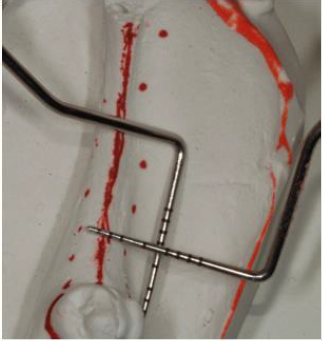

Unfortunately, the 3D evaluation showed a severe type of horizontal bone resorption in both molar areas, right and left. Priority was given to the lower left side where one bicuspid and all three molars were missing. Nevertheless, the anatomy of the area showed how the combination of horizontal bone loss plus very superficial mandibular canal would allow the placement of one only implant. As part of the planning, stone casts were taken and with the aid of periodontal probes was evaluated the kind of augmentation needed (Figure 5). In order to accommodate a standard diameter implant was requested an augmentation of at least 5-6 mm. It was decided to address this area with the aid of a bone lamina (Cortical Lamina, OsteoBiol by Tecnoss, Coazze, Italy) technique associated with a mix of autogenous bone mixed with collagenated porcine bone graft (GenOs, OsteoBiol by Tecnoss, Coazze, Italy) [2].